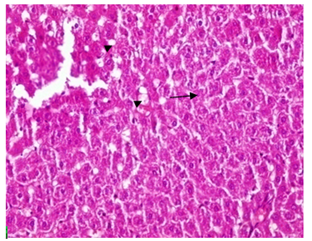

Fig. 2A represented a liver section of the negative control group; it showed a normal hepatic lobular architecture with rounded or polygonal hepatocytes arranged in lobules with elongated blood sinusoids and normal central vein. The hepatocytes exhibited rounded nuclei located either central in the cytoplasm. Treatment of mice with Mal (27 mg/kg)resulted in dilation of the hepatic blood vessels (arrow), hepatocytes appeared irregularly distributed and displayed drastic pathological alterations, clear signs of necrosis, the nuclei disappeared from most of the cells and the cytoplasm became vacuolated or greatly liquefied as shown in fig. 2B. While Atra (120mg/Kg) treatment leads to severe hepatic damage represented by fatty change of hepatocytes with vaculation (arrow heads), necrosis in liver cells in the form of pyknotic nuclei (arrow), markedly increased of endothelial cells in different parts of the hepatic tissue and more eosinophilia of the cytoplasm (fig. 2C). Fig. 2D and 3A represent PPE and PJ groups respectively, they show normal central veins surrounded by cords of hepatocytes with central vesicular nuclei and eosinophilic cytoplasm. They show normal hepatic lobular architecture that is more or less as the negative control group. This means that neither PPE nor PJ has a damaged effect on the hepatic architecture, in another meaning, they have no hepatic side effects.

Fig. 2: Photomicrographs of liver section of different mice groups. In which A, represents negative control group; B, Mal group; C, Atra group and D, PPE group. H&E (X200)